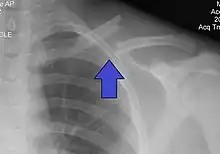

X-ray of a left clavicle fracture

A clavicle fracture, also known as a broken collarbone, is a bone fracture of the clavicle.[1] Symptoms typically include pain at the site of the break and a decreased ability to move the affected arm.[1] Complications can include a collection of air in the pleural space surrounding the lung (pneumothorax), injury to the nerves or blood vessels in the area, and an unpleasant appearance.[2]

It is often caused by a fall onto a shoulder, outstretched arm, or direct trauma.[1][3] The fracture can also occur in a baby during childbirth.[1] The middle section of the clavicle is most often involved.[3] Diagnosis is typically based on symptoms and confirmed with X-rays.[2]

The basic method to check for a clavicle fracture is by an X-ray of the clavicle to determine the fracture type and extent of injury. In former times, X-rays were taken of both clavicle bones for comparison purposes. Due to the curved shape in a tilted plane X-rays are typically oriented with ~15° upwards facing tilt from the front. In more severe cases, a computerized tomography (CT) or magnetic resonance imaging (MRI) scan is taken. However, the standard method of diagnosis through ultrasound imaging performed in the emergency room may be equally accurate in children.[5]